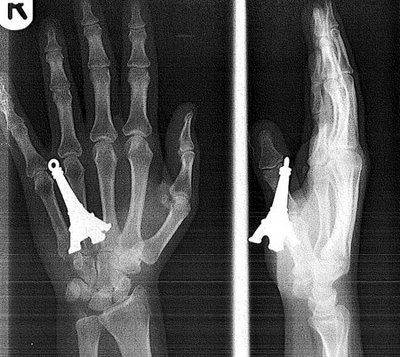

1. Un porte-clef Tour Eiffel dans la main

L’expression « avoir quelqu’un dans la peau » prend tout son sens.